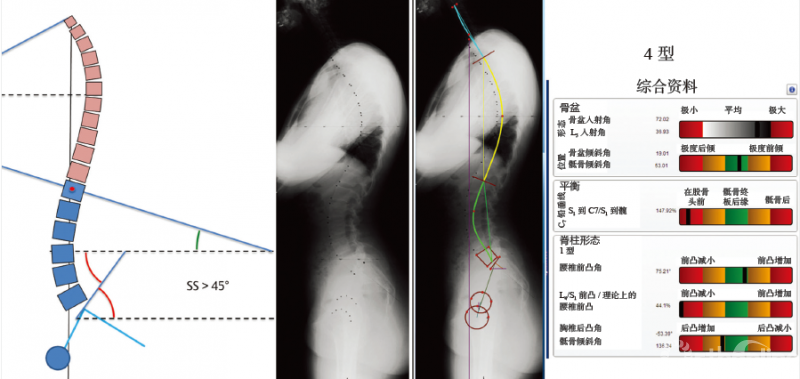

4型脊柱前凸(图6-13):特征是具有较高的骶骨倾斜角(>45°);腰椎前凸的顶点位于L3或更高的椎体;处于前凸范围内的椎体≥5个节段,且存在节段性过伸状态。

图 6-13 4型脊柱前凸

骶骨倾斜角>45°,前凸侧的椎体数目大于5个节段,存在节段性过度伸展状态